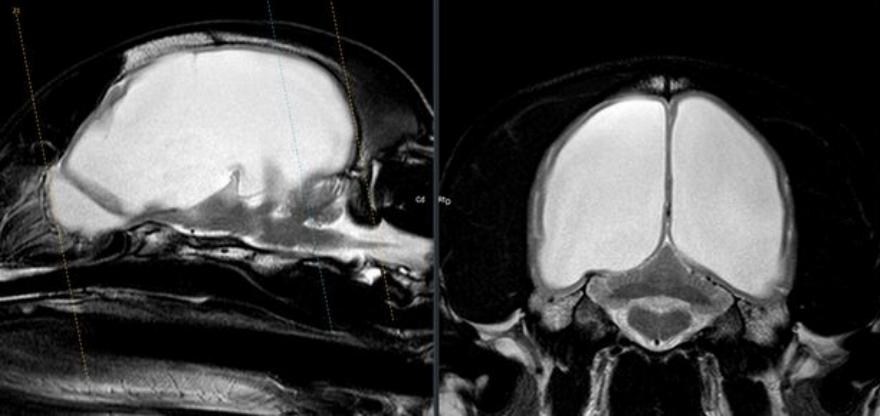

Η τύφλωση του Gus προκλήθηκε από πίεση που μεγάλωνε στο εσωτερικό του εγκεφάλου του, σύμφωνα με τα αποτελέσματα της ακτινογραφίας.

Η ίδια δήλωσε: “Ο Gus είναι ένας από τους πιο σημαντικούς ανθρώπους που έχω γνωρίσει ποτέ. “Ο Gus έκανε μαγνητική τομογραφία και αξονική τομογραφία και η Alexandra έμεινε έκπληκτη. Είπε ότι ήταν η μεγαλύτερη περίπτωση υδροκεφάλου (υγρό στον εγκέφαλο) που είχε δει ποτέ και είχε κατακλύσει και τις δύο πλευρές του εγκεφάλου του.

“Ήμουν σοκαρισμένη και δεν μπορούσα να φανταστώ τον πόνο που υπέφερε, αλλά η Alexandra είπε ότι υπήρχε τρόπος να αποστραγγιστεί το υγρό και να μειωθεί η πίεση στα μάτια και τον εγκέφαλο του Gus“.